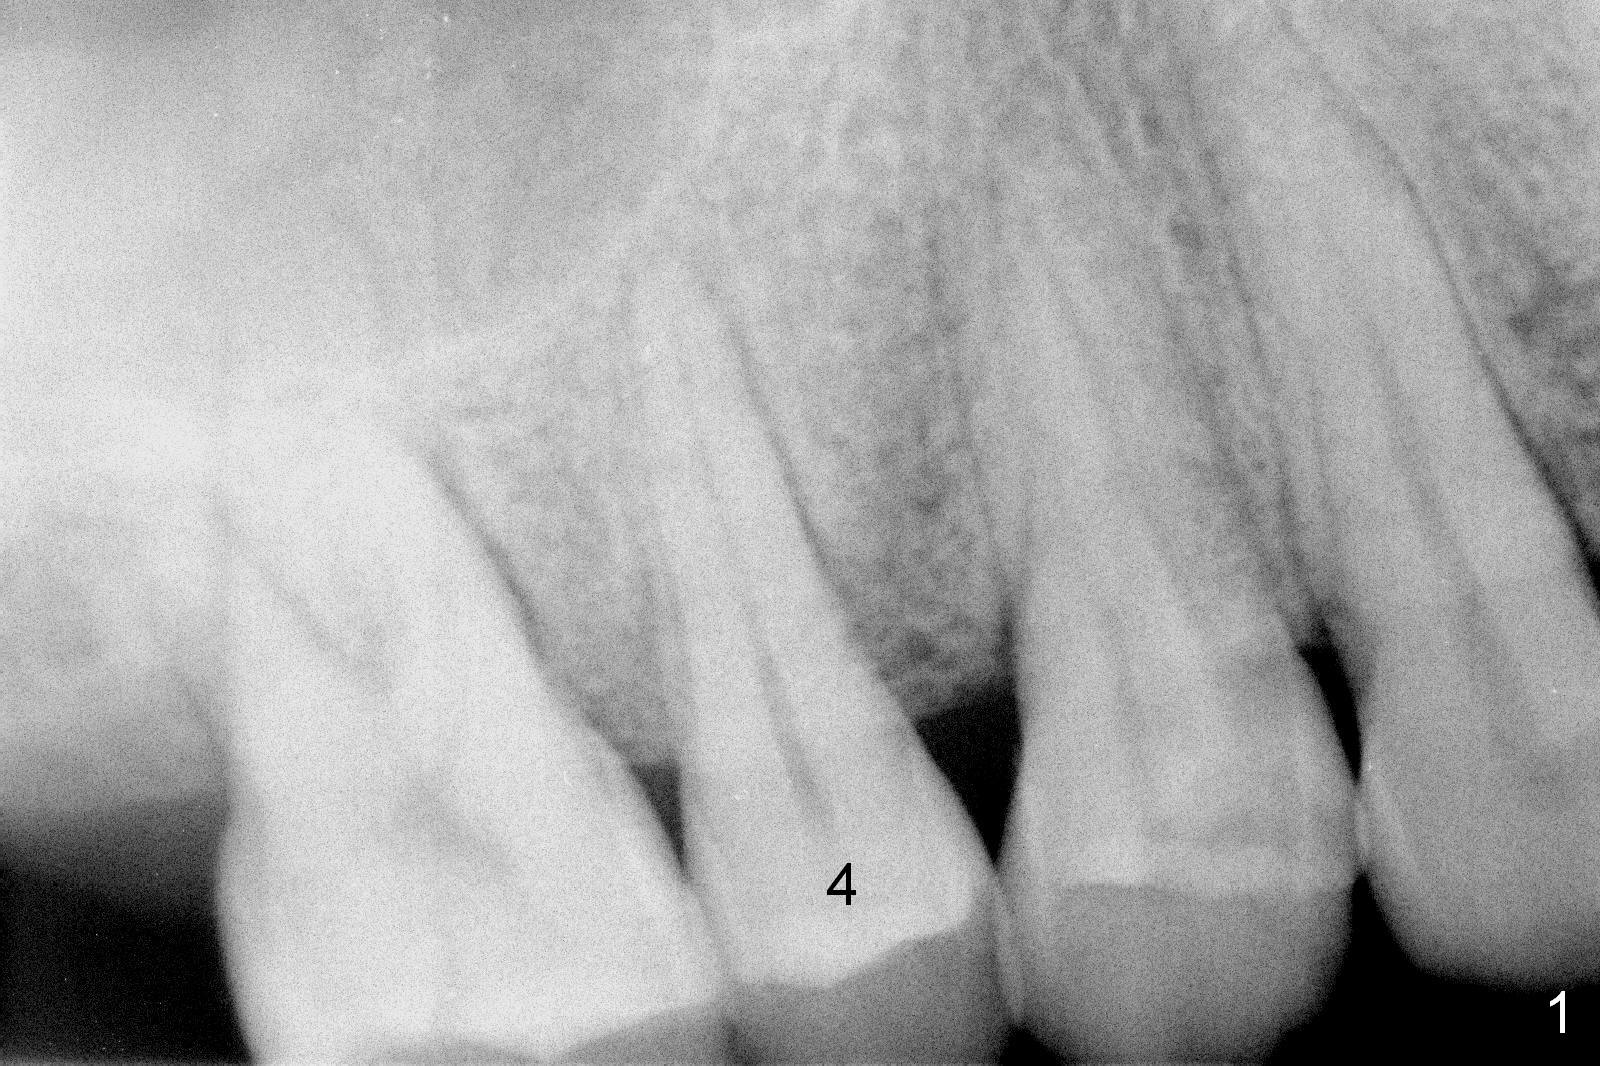

A 47-year-old man returns emergently with subgingival fracture of the lingual (L) cusp of the tooth #4 (Fig.1-3). After extraction (no bony defect) without drilling, a 4x11 mm dummy implant is placed as a tap drill with satisfactory stability (Fig.4,5). To get subcrestal placement, a shorter (4x9 mm) implant is inserted with insertion torque of < 35 Ncm. In retrospect, a larger implant (4.5 mm) would be better in term of primary stability. After allograft placement into the buccal and lingual gaps, a 4.5x4(4) mm abutment is placed for an immediate provisional. There is a peri-implant gap 7 months postop (Fig.7<, as compared to the implant at #2 (6 months postop)) . When the loose abutment is being retightened, the patient feels pain, although the gingiva appears healthy (Fig.8). A larger implant should have been used; the abutment should have been removed. The implant dislodges while the abutment is untightened 8 months postop. The osteotomy is found intact. A 4.5x11 mm dummy implant is placed 2 mm subgingival with 20 Ncm (Fig.9). When a 4.5x11 mm definitive implant is placed 3 mm subgingival (Fig.10,11), torque reaches 50 Ncm. A 5.5x3 mm healing abutment is placed. Three months postop, the implant is stable (Fig.12,13) and impression is taken.